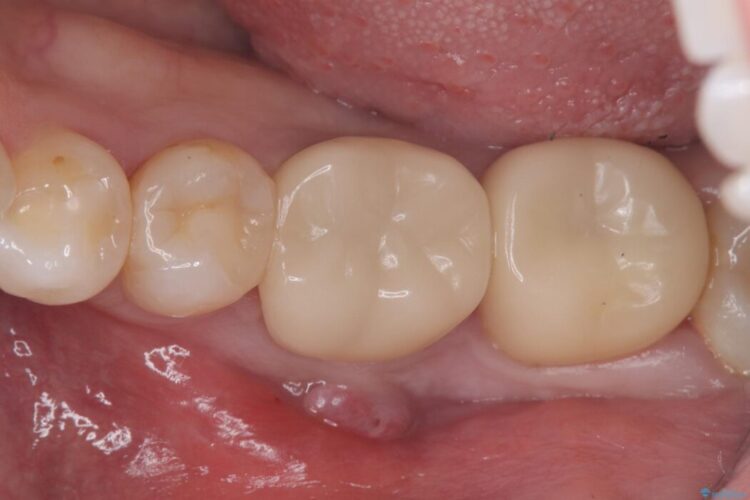

保存が難しい左下6番を抜歯し、左下8番(親知らず)を抜歯窩に移植しました。歯牙移植後の動揺防止のため暫間固定を行っています。

骨との定着を確認し、今後矯正治療を行う予定のためレジン冠をセットしています。